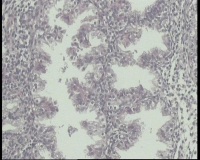

| 图片: | |

- 急!请老师看看34岁子宫内膜

| 性别 | 女 | 年龄 | 34岁 | 临床诊断 | 子宫内膜息肉? |

| 一般病史 | 末次月经:11月20日,近两个月无诱因性生活有阴道少许血性分泌物 | ||||

| 标本名称 | 宫内容物 | ||||

| 大体所见 | 膜样碎组织3.0厘米 | ||||